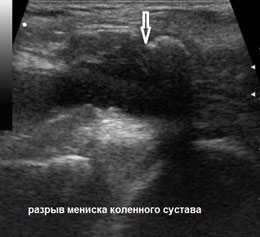

- УЗИ-диагностика. Считается малоэффективным, потому что правильность и точность полученных результатов диагностики во многом зависит от опыта и квалификации доктора;

- МРТ - более надежный метод выявления повреждений хряща. МРТ показывает, в каком состоянии находится мениск, сложность травмы (надрыв или полный разрыв).